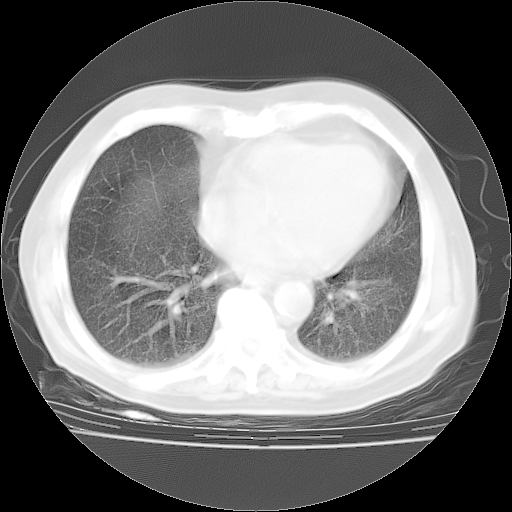

4月28日肺部CT——再次出现类似去年5月9日——透光度降低,“间质性”改变。

4月28日肺部CT——再次出现类似去年5月9日——磨玻璃样、间有“粟粒样”改变。